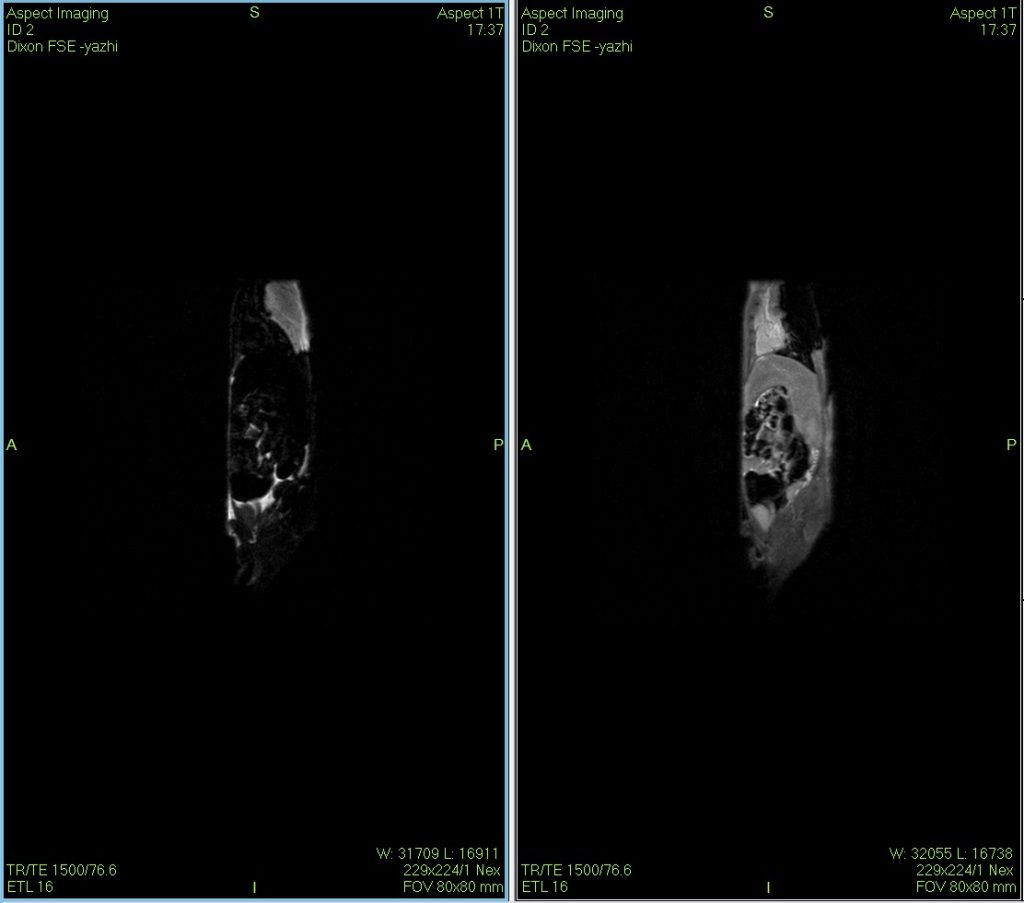

Dixon water–fat imaging of a mouse using MRI

The Dixon water–fat separation technique is a versatile MRI method with unique value in diagnosing, differentiating, and evaluating therapeutic responses in certain animal disease models.